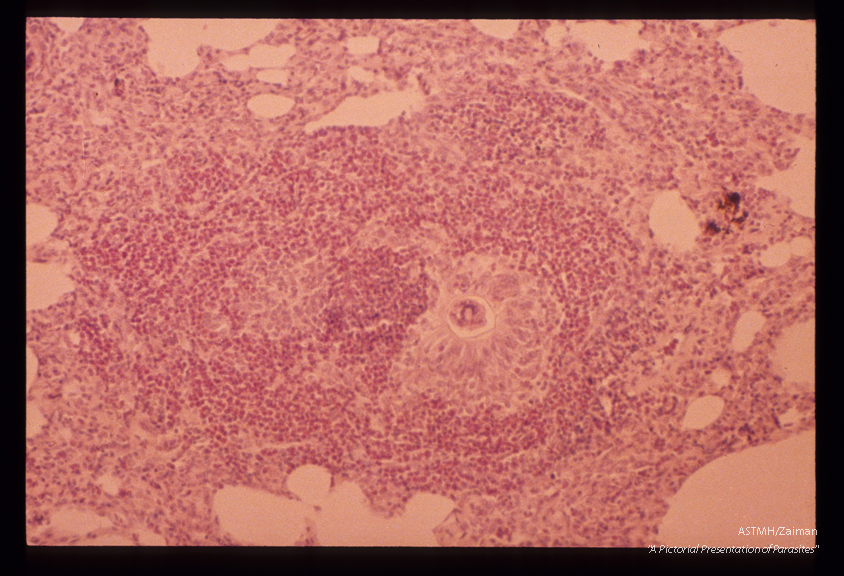

Egg in monkey lung. A granuloma containing an egg shell is seen in the lung. Note the marked esosinophilic infiltrate.

Schistosoma japonicum

Description: Egg in monkey lung. A granuloma containing an egg shell is seen in the lung. Note the marked esosinophilic infiltrate.